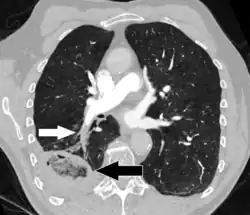

-

Pulmonary embolism (white arrow) that has been long-standing and has caused a lung infarction (black arrow) seen as a reverse halo sign